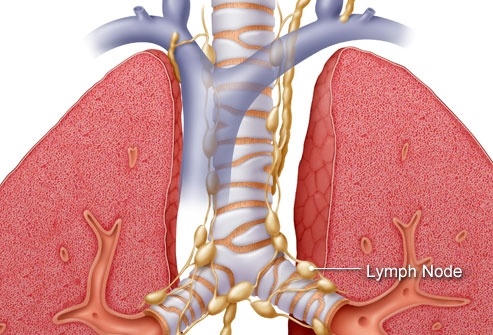

Mỗi loại ung thư phổi có cách xâm lấn khác nhau trong cơ thể. Như ung thư phổi tế bào nhỏ được chia thành hai giai đoạn: Giai đoạn giới hạn có nghĩa là ung thư được giới hạn trong một phổi và các hạch bạch huyết có thể ở gần vị trí khối u. Giai đoạn ung thư lan rộng có nghĩa là ung thư đã lan rộng khắp phổi hoặc ra các bộ phận khác. Ung thư phổi không phải tế bào nhỏ được chia thành từ 1 đến 4 giai đoạn, tùy thuộc vào việc khối u lan rộng đến đâu.